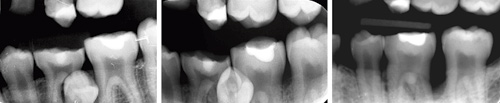

Kasusrapport Diagnosestilling og behandling av festetap med benlomme hos en ung pasient Festetap på tenner hos ungdommer forekommer sjelden. Finner man festetap på en permanent tann hos en ung pasient, er det viktig å stille riktig diagnose. Årsaker til tap av ben rundt permanente tenner er mange. I de fleste tilfeller hvor bentap er lokalisert marginalt, er periodontal sykdom årsak, men også andre tilstander kan føre til tap av ben og feste. Denne artikkelen beskriver et pasientkasus hvor en paradental cyste har forårsaket bentap. Artikkelen belyser problemstillinger i diagnosesetting og gir en kort oppsummering av forskjellige differensialdiagnoser for marginalt bentap ved permanent tann. Les artikkel